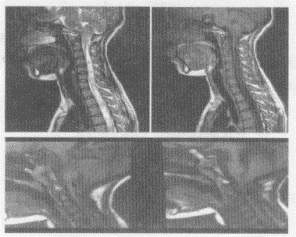

1.MR對(duì)先天性脊髓空洞與腫瘤繼發(fā)的脊髓空洞的主要鑒別是

正確答案:D 解題思路:腫瘤繼發(fā)性脊髓空洞癥的空洞壁有腫瘤組織,可以發(fā)生強(qiáng)化。

5.患者,男,30歲,兩手乏力、發(fā)麻,結(jié)合圖像,最可能的診斷是

正確答案:A